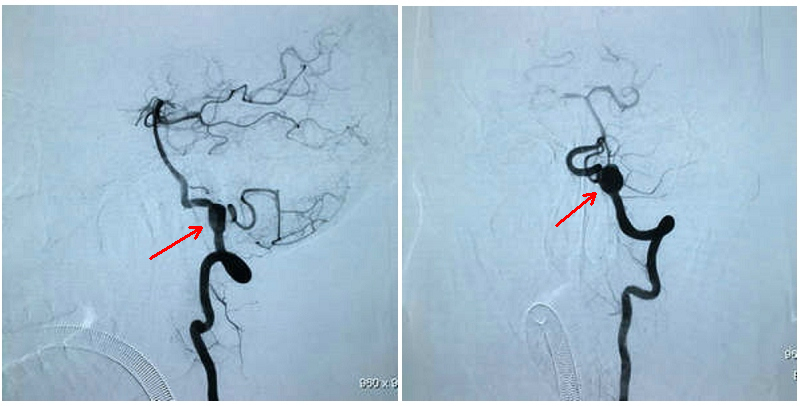

术前造影结果(红箭头指动脉瘤)